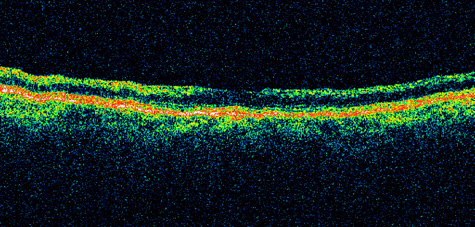

Fig. 1. A: Acute central retinal artery obstruction with a cherry-red spot. B and C: Intravenous fluorescein angiography. There is a delay of dye appearance in the central retinal artery, and when it does appear, it does not fill the arteries completely. D: Ocular coherence tomography (OCT) at the time of occlusion showing the increase in retinal thickness and reflectivity of the inner layers of the retina. E: Seven months later there is significant optic atrophy(G), and the OCT (F) shown now has marked thinning of the retina.

Optic coherence tomography (OCT) of an acute central retinal artery occlusion shows a slight increase in the thickening of the retina and reflectivity of the inner layers of the retina that correspond to the opacity seen clinically (Fig. 1).409 With time, the disc becomes atrophic and the retina thinner.